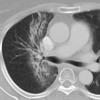

Radiation case 2

Date: 02/10/2005

Views: 3982